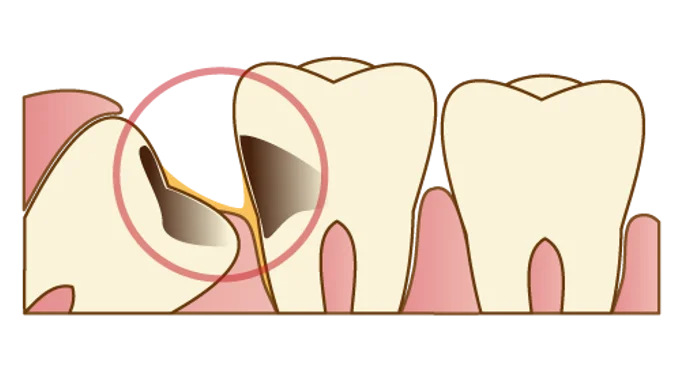

2.歯並びに悪影響が出ている

親知らずはこのように横向きに生えることが多いです。 横向きに生えた親知らずは手前の歯をグイグイと押し、歯並びに悪影響を与えることがあります。